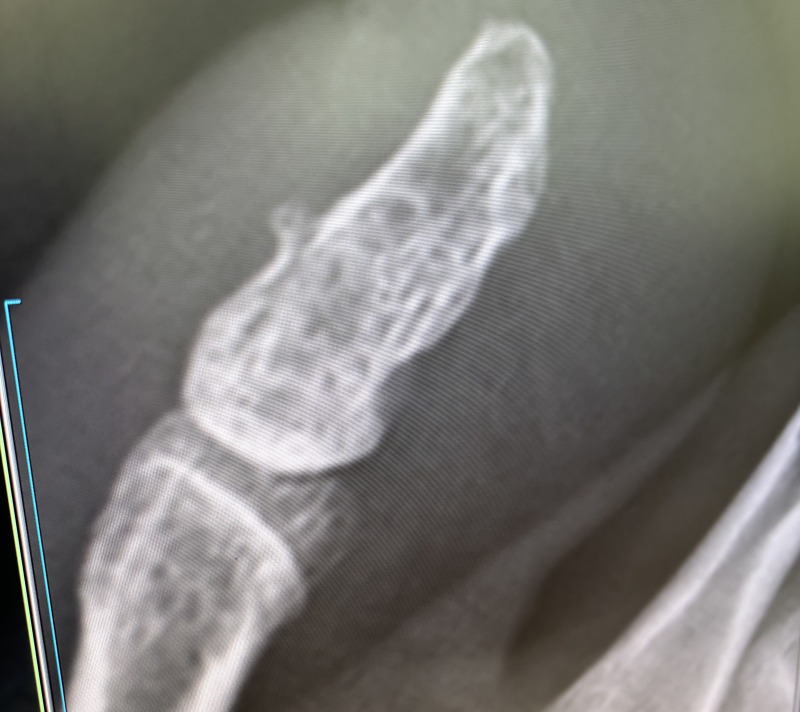

病院で正式に「骨折」が認定される

帰国翌日に病院を受診。

レントゲン取って、無事に(?)骨折が認定されました。

全治1ヵ月!

え、そんなにかかるの?ってびっくり。

どうやらキレイに折れてたらしく、治療はテーピングのみで、シップとロキソニンが処方されました。